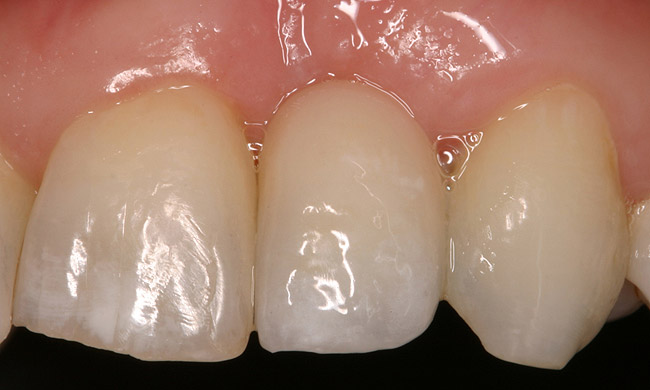

Figure 5a  Congenitally missing lateral incisors. Postorthodontic therapy, prior to implant placement.

Figure 5a

Figure 5b  Congenitally missing lateral incisors. Postorthodontic therapy, prior to implant placement.

Figure 5b